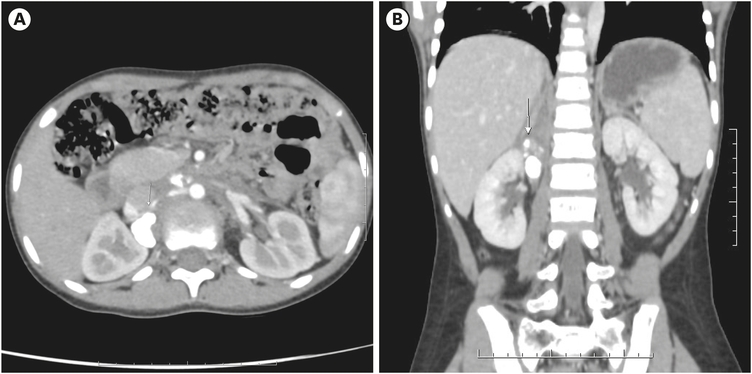

Image-guided core needle biopsy revealed a malignant round cell tumor with immuno histochemistry study positive for synaptophysin, neurofilament, CD56; negative for CD99, desmin, keratin, and leukocyte common antigen with a Ki67 value of 90%, suggestive of neuroblastoma, undifferentiated type with low mitotic karyorrhectic index (<2%). Fluorescence in situ hybridization was positive for N-MYC gene amplification. Bone marrow biopsy was suggestive of marrow involvement by malignant round cells. Diagnosis of stage IV Neuroblastoma - high risk was confirmed, and she was treated as per Children’s Cancer Group (CCG) 3891 protocol [3]. She received six cycles of neoadjuvant chemotherapy. Post-chemotherapy imaging revealed a partial response of the primary with residual retroperitoneal nodes (Fig. 1). She underwent open right adrenalectomy with retroperitoneal lymph node dissection (RPLND). Histopathology was reported as Neuroblastoma with treatment effect - viable tumor being 30%. The resected margins were free of tumors, RPLND - 10 of 10 lymph nodes had metastatic Neuroblastoma with extranodal extension.

Fig. 1

Preoperative contrast enhanced computed tomography of the abdomen: images showing a large right suprarenal tumour with extensive calcification, marked by arrow head. (A) Axial, (B) coronal.